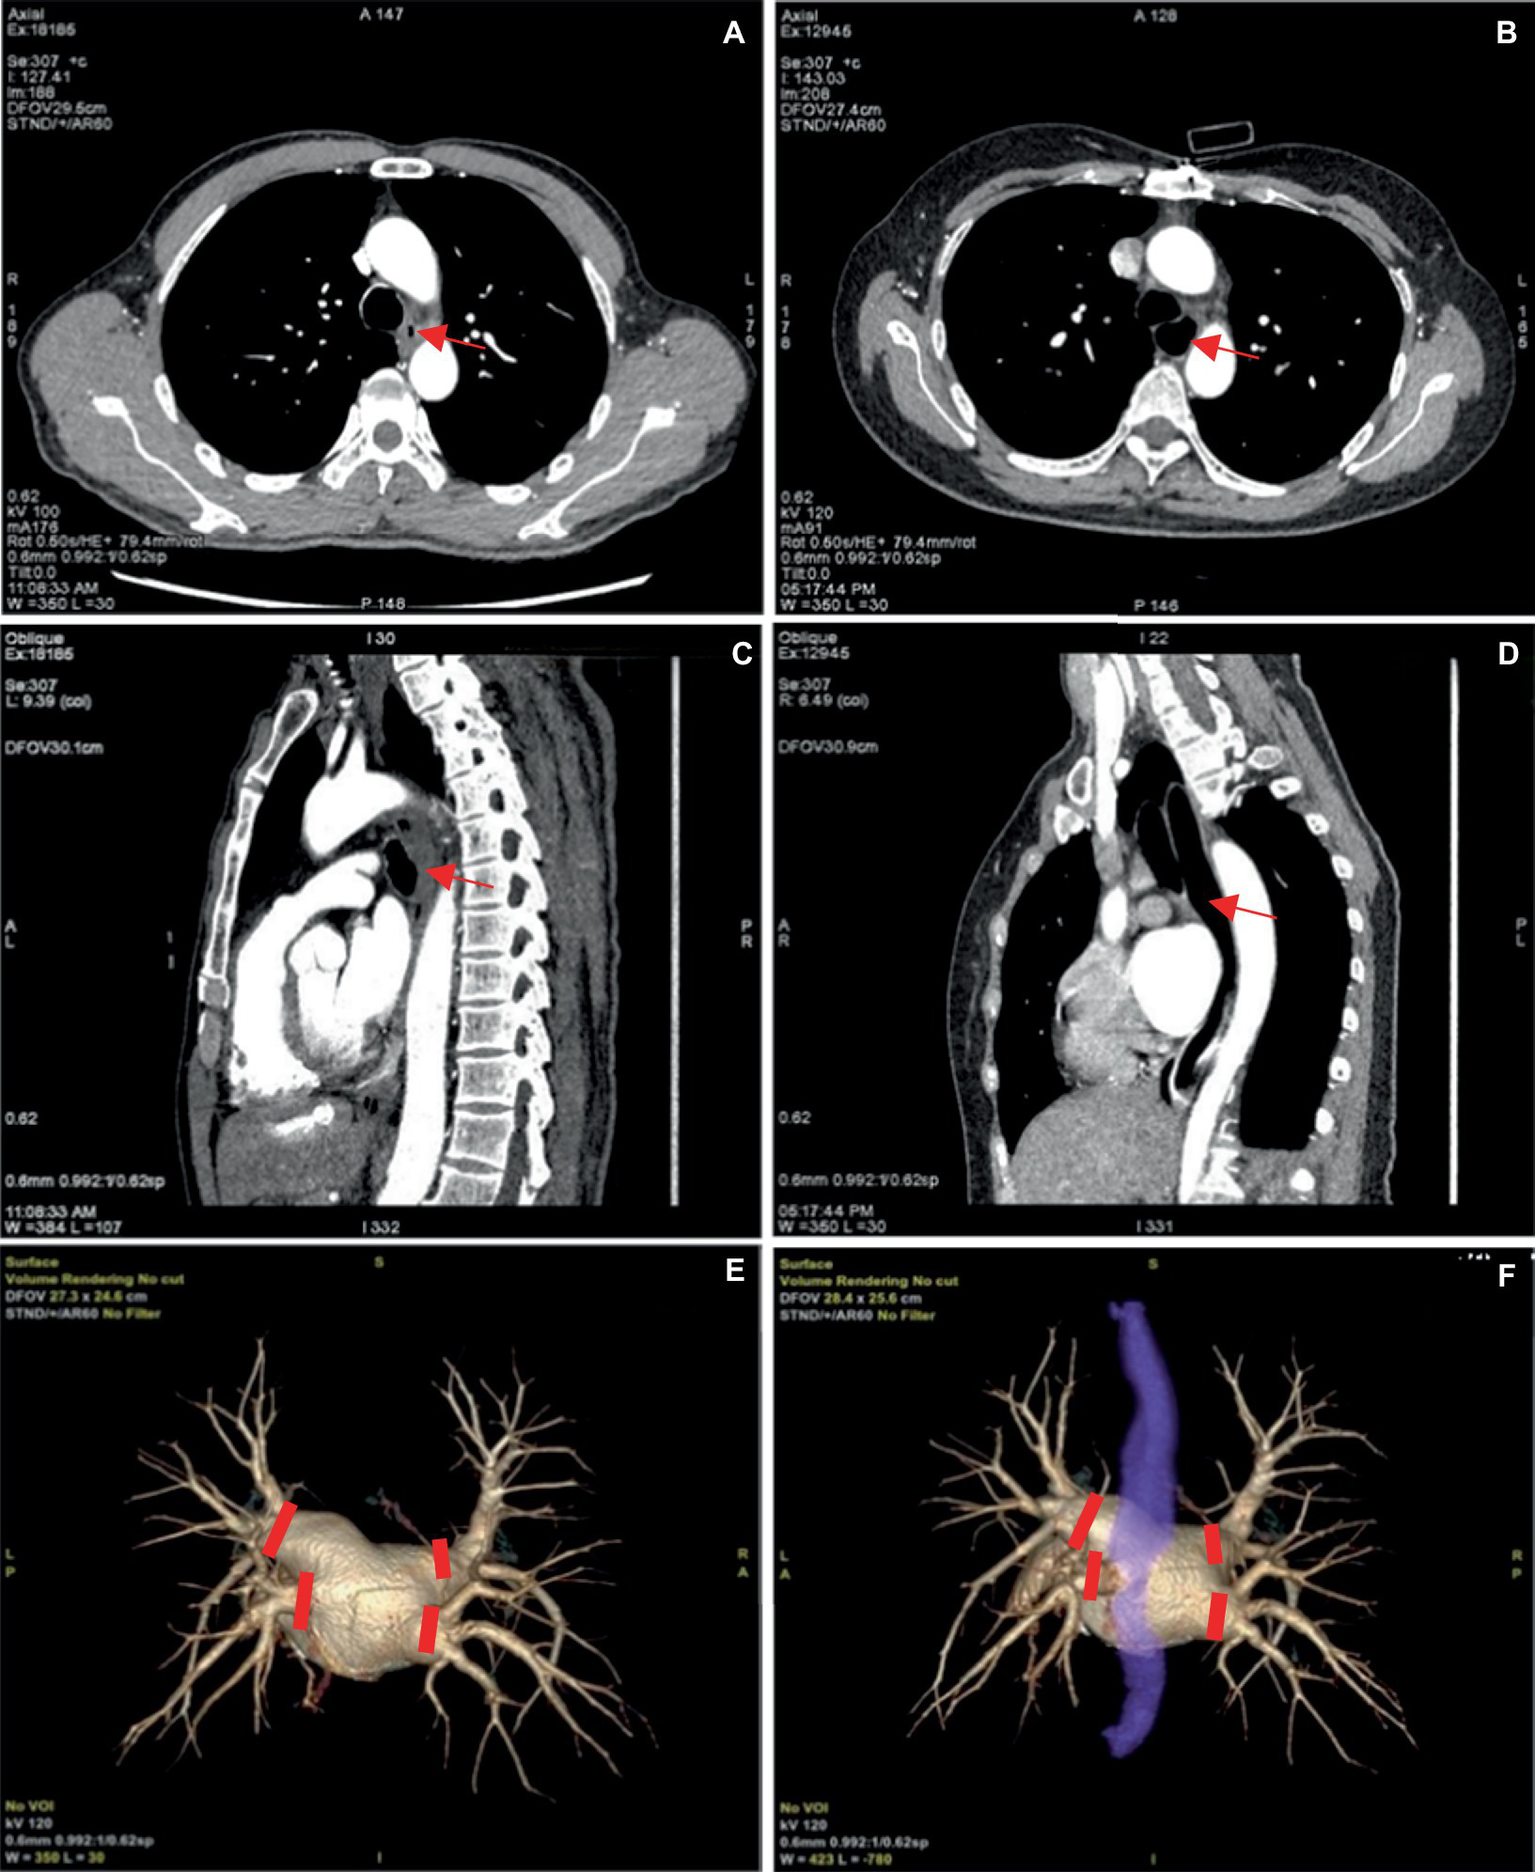

Our attempts enabled convenient visualization of the anatomical relation of the esophagus (blue, Figure 6). The esophagus is in a constricted state during non-feeding conditions, leading to indistinct of the boundary between the esophageal wall and the surrounding soft tissue during reconstruction, and low CNR and SNR of the image. Expanding the esophagus during image acquisition may facilitate image reconstruction. For this purpose, the patients were asked to wrap a mouthful of diluted iodine contrast agent in the mouth and follow the voice instructions to swallow during image acquisition. This approach significantly enhanced esophageal expansion, however, the high density of the diluted iodine contrast agent resulted in partial sclerosis artifacts surrounding the esophagus and we excluded this method. Subsequently, we employed water-swallowing, which effectively dilated the esophagus without compromising the SNR. For radiofrequency ablation surgeons, the three-dimensional fusion images in the water-swallowing group exhibited significantly superior quality compared to those in the calm-breathing group. However, it is more difficult for elderly people to undergo swallowing tests. For example, in our study, there was an 80-year-old man who did not respond to the swallowing instruction during the examination. Though his esophageal dilation was not perfect, we included the case in the study because it reflects the current needs.

Figure 6

(A,C) Represent the pulmonary venous phase axial and sagittal images of the same patient, with calm breathing during image acquisition. And the esophagus is seen in a contracted state at the arrow. (B,D) Depict the pulmonary venous phase axial and sagittal images of the same patient with water-swallowing during image acquisition. And well-filled and expanded esophagus is indicated at the arrow. (E) Shows the three-dimensional reconstructed image of the pulmonary vein. (F) Depicts the fusion image of the left atrium, pulmonary vein, and esophagus in a water-swallowed patient, with an esophagus stained blue. The four red markers indicate the points for pulmonary vein isolation during radiofrequency ablation for atrial fibrillation.